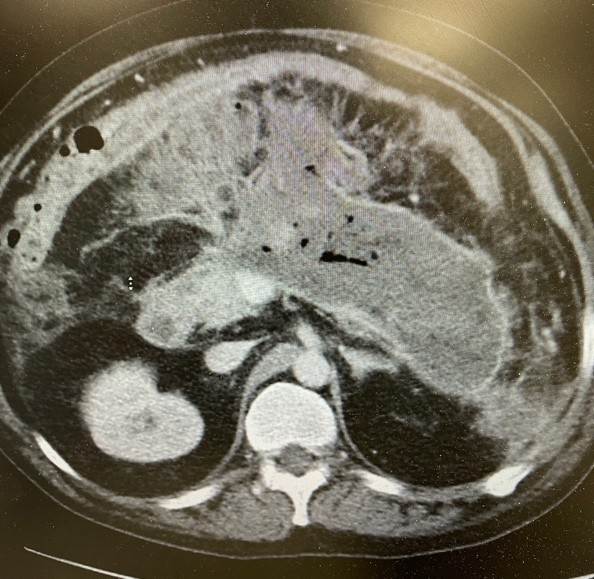

The patient is a 44-year-old male who was initially admitted to the hospital in October 2024 for alcohol-induced acute necrotizing pancreatitis. He was managed by supportive care and he was able to be discharged after 10 days of hospitalization. He was admitted after three weeks of illness with fever, chills and increasing abdominal pain and poor oral intake. CT imaging study showed air in the pancreatic necrotic cavity measuring 24.8 cm x 11.6 cm (Figure 1). EUS-guided drainage was performed using 20 mm x 10 mm lumen apposing metal stent (LAMS), hot Axios (Boston Scientific Corp). The necrotic cavity was visualized using linear array echoendoscope (Olympus America) and using the electrocautery tip of the stent, the wall of the necrotic cavity was punctured from the stomach; the distal flange was deployed inside the cavity and the proximal end of the stent was released under endoscopic guidance.

Figure 1. Infected walled off necrosis. Gas inside the cavity indicating a sign of infection.

Figure 1